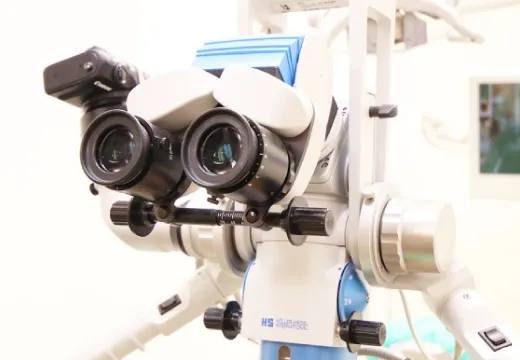

2種類のマイクロスコープ

当院は、2種類のマイクロスコープを使用しています。

・「マイクロスコープ ユニバーサ300改」は、フットフォーカス付の高性能マイクロスコープ。高い汎用性で、使い勝手に定評があり、新型が投入された現在でも旧モデルを探す声が後を絶たない人気機種。当院のモデルはさらにキセノン光源を追加し、改造した架台に取り付けいつでも切り替え可能になっています。

・「OPMI pico MORA」は、カールツァイス製、オムニピコモラー・フォルダブル鏡筒タイプです。

見えるからこそできる治療

ルーペは常時、さらに拡大が必要なときにはマイクロスコープ(歯科用実態顕微鏡)、拡大歯科治療は当院の標準装備です。見えるからこそ出来る、治療のクオリティーで来院をお待ちいたしております。

なるべく削らない。削ったらきちんと修復する。当たり前のことですが、常に誤差が生じるため、これをしっかり実行するのは大変難しいものです。マイクロスコープやルーペを用いて視野を拡大するのもそのひとつの方法です。

院長が常時使用しているルーペは3.5倍、さらに拡大が必要な場合は7倍です。当初はこれで十分と考えていました。マイクロスコープを導入するまでは…。

マイクロスコープを使いこなせるようになった現在いえることは、倍率よりもはるかに見えるものがあるということです。ルーペの3.5倍よりマイクロスコープの2倍の方が、またルーペの7倍よりマイクロスコープの4倍の方がはるかに見えるものが多い…。これは、マイクロスコープのレンズのクオリティーのなせる業だと考えています。同じものを見てもさらに違った発見がある。これこそがマイクロスコープクオリティなのです。 さらに最近解かったことは、拡大診療に慣れれば慣れるほど、治療精度が上がったまま治療時間は短くなっていくということです。当院では、かねてから定評のある「メーラー社製 ユニバーサ300」を導入しています。さらに、明るさが求められる根の治療用にキセノンランプ補助光源も特注。精密な歯科治療に対応しています。